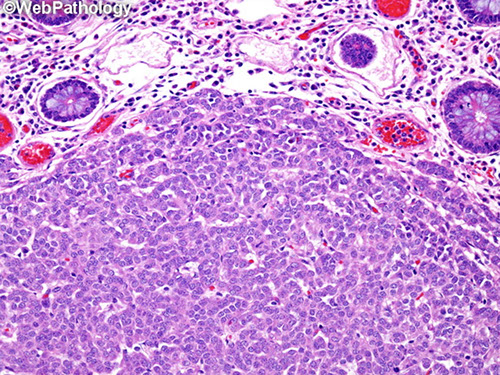

- superficial portions of WDNT can be subtle, usually not assoc c inflam dz (as in the stomach)

~1/3 sm bowel neoplasms, esp in blacks

- derive from foregut (duodenum) and midgut (Jej and Ileum); accounts for variable clinical behavior and NE differentiation

2nd MCC cancer in duodenum (usually in bulb); in older males; 2/3 make gastrin (1/3 of which get ZE), rest are somatostatin-producing (1/3 assoc c NF1) or D-cell tumors

- usually small polypod lesions (<2 cm) in submucosa

- prox sm bowel carcinoids almost never cause carcinoid syndrome

- rare small cell carcinomas (HG-NE tumors) usually found around ampulla and have poor px

In midgut, NE tumors usually are EC cell or serotonin-making, and usually found in ileum; and can produce carcinoid syndrome (1/20; these are the MCC of carcinoid)

- tumors more likely to be multicentric and large; usually found at more advanced stage and cause mesenteric fibrosis and obstruction

- midgut WDNT's malignancy is based on whether or not there are mets or not, rather than just histologic eval (clinically malignant tumors may not have pleomorphism, hyperchromasia or inc mits

Micro: WDNTs are monotonous prolif of small bland polygonal cells c mod amt cytoplasm; round regular nuclei and salt n peppa chromatin

- have variable architectural patterns (A = nested/insular; B = trabecular; C = acinar)

- D-cell tumors usually have prominent acinar growth pattern c intraluminal psammoma bodies

- HG-NEC, small cell type has prominent crush artifact and inc mits